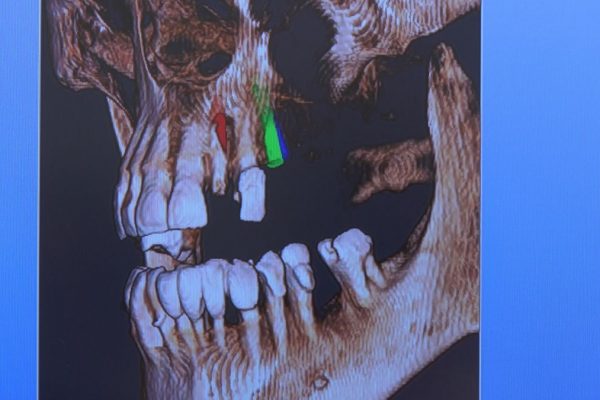

W ostatni weekend czerwca 2018 roku kursanci II Sezonu Preludium Implantologii odbyli piątą, finałową sesję, która w całości podporządkowana była praktyce. W ciągu dwóch dni zabiegowych Lekarze uczestniczący w szkoleniu przeprowadzili szereg zabiegów pod kierunkiem dr n.med. Violetty Szycik. Wszczepili 17 implantów oraz przeprowadzili ekstrakcje i zabiegi regeneracyjne kości. Zabiegi były wykonywane także w sedacji dożylnej z udziałem specjalisty anestezjologii i intensywnej terapii dr Jolanty Grzybowskiej. Preludium implantologii to nowy program edukacyjny dla adeptów implantologii stomatologicznej, którego celem jest wprowadzenie do implantologii poprzez pozyskanie wiedzy w szerokim zakresie i uwzględnieniem szczegółów mających decydujące znaczenie dla powodzenia leczenia implantologicznego. Ale tak jak wszystkie szkolenia w Instytucie Vivadental, w tym wiodące Practiculum Implantologii, zorientowane jest na praktyce i samodzielnym wykonywaniu zabiegów pod kierunkiem Mentora. To najlepsza edukacja w medycynie zabiegowej, a zarazem najlepszy start do implantologii.